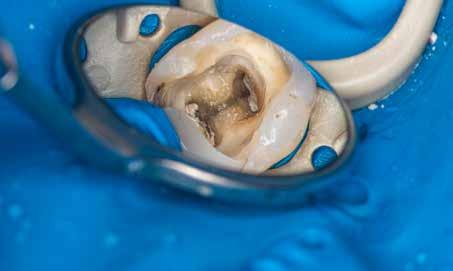

A terület érzéstelenítése és a kofferdám felhelyezését követően az ideiglenes tömést eltávolítottuk, majd a fogbélkamrát 5,25%-os NaOCl-oldattal feltöltöttük, amelyet ultrahang segítségével aktiváltunk (4–5. ábra). A fogbélkamrában lévő visszamaradt szuvasság eltávolítását követően a területet vízzel lemostuk, majd az egész területet puszterrel leszárítottuk. A terület előkészítését követően az izolálást

ábra: Kiindulási röntgen. A felvételen jól látható a betört eszköz és a periapikális lézió.

2. ábra: Kiindulási CBCT-felvétel. A betört eszköz mélyen a gyökércsatorna görbülete mögött található.

3. ábra: A betört eszköz vége jóval a mesiobuccalis és mesiolinguális csatorna egyesülésének pontja alatt helyezkedik el.

4. ábra: A kofferdám felhelyezése után látható állapot. Az ideiglenes tömés még nem került eltávolításra.

5. ábra: Az ideiglenes tömés eltávolítását követően látható állapot.

6. ábra: A visszamaradt szuvas foganyag eltávolítását és a folyékony kofferdám felhelyezését követően kialakult helyzet.

folyékony kofferdám felvitelével tökéletesítettük, majd polimerizáltuk. Ezt követően a lézeres kezelés előkészítése részeként a hozzáférési nyílás méretét megnöveltük (6. ábra). A lézeres aktivációhoz egy SkyPulse lézerkészüléket (Fotona) használtunk AutoSWEEPS üzemmódban. Egy lapos végű 300/20 SWEEPS hegyet 1 W teljesítmény mellett alkalmaztunk (7. ábra). A fogbélkamrát NaOCl-oldattal feltöltöttük, majd a vezetőszál hegyét enyhén a mesiobuccalis csatorna